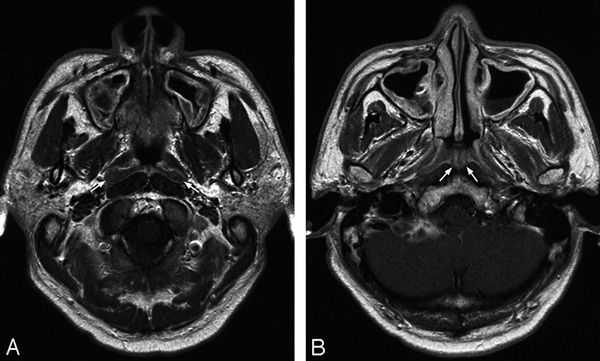

Магнитная томография околоносовых пазух: левосторонний сфеноидит